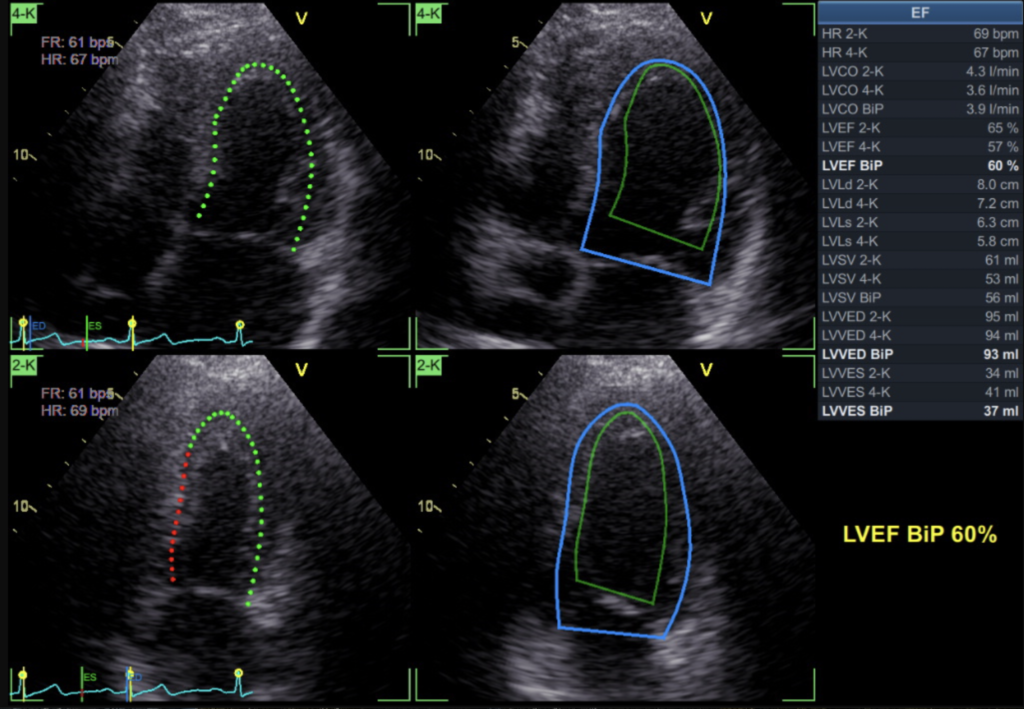

Der Herzultraschall ist eine Ultraschalluntersuchung des Herzens. Sie hilft, die Struktur und Funktion des Herzens zu beurteilen. Es gibt verschiedene…

Weiterlesen